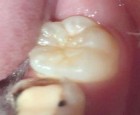

Bệnh nhân: Trần Nguyệt H. 7 tuổi, Răng 46, mã BA 11907/17

Sau sáu tháng. ICDAS: 1; Di: 15 | Sau chín tháng. ICDAS: 0; Di: 13 | Sau 18 tháng. ICDAS 0; Di:7 |